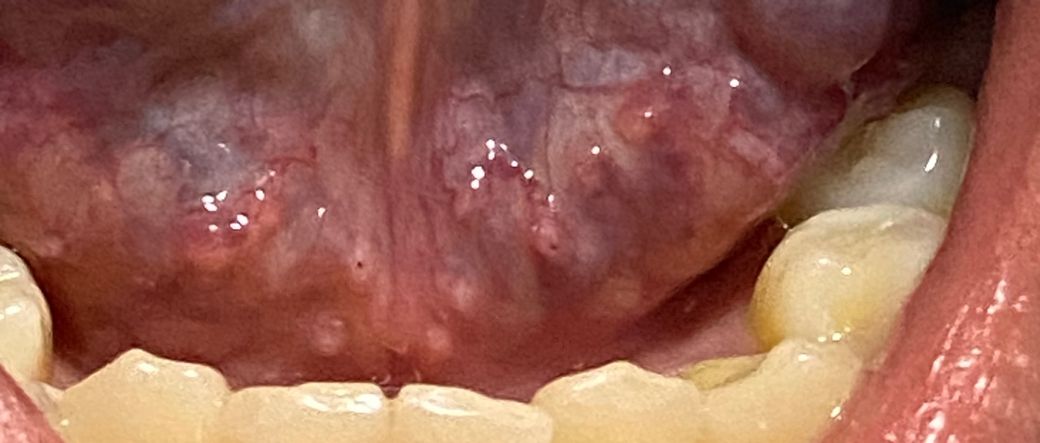

혀 밑에 수포?돌기? 같은게 작게 났는데 뭔지 모르겠어요

혀 옆에 구내염이 생겨서 혀 구석구석 봤는데

혀 아래에 작게 따닥따닥 뭐가 난 걸 발견했습니다

건드렸을 때 가렵지도 아프지도 않은데 뭔지 알 수 있을까요??? 병원에 가서 진료받아야 할까요???

그리고 혀 아래에 빨갛게 동그라미친 부분은 누르면 아픈데 크기가 저렇게 작아도 구내염이라고 볼 수 있나요??

• 2번 째 사진

올려주신 상기 병변은 질환에 의한 병변이 아니며 혀점막의 정상적이 구조물과 판단이 됩니다. 혀나 구강 점막은 다양한 형태로 나타날 수 있는데 표면의 결절성 변화나 궤양이 형태로 나타난다면 염증 병변과 종양성 병변에 대한 감별이 필요합니다. 하지만 올려주신 사진상 이러한 특징적인 소견은 관찰되지 않으므로 정상적인 점막의 변화로 판다할 수 있습니다. 따라서 증상이 없다면 진료 없이 경과 관찰이 가능하므로 너무 걱정하지 않으셔도 되겠습니다.